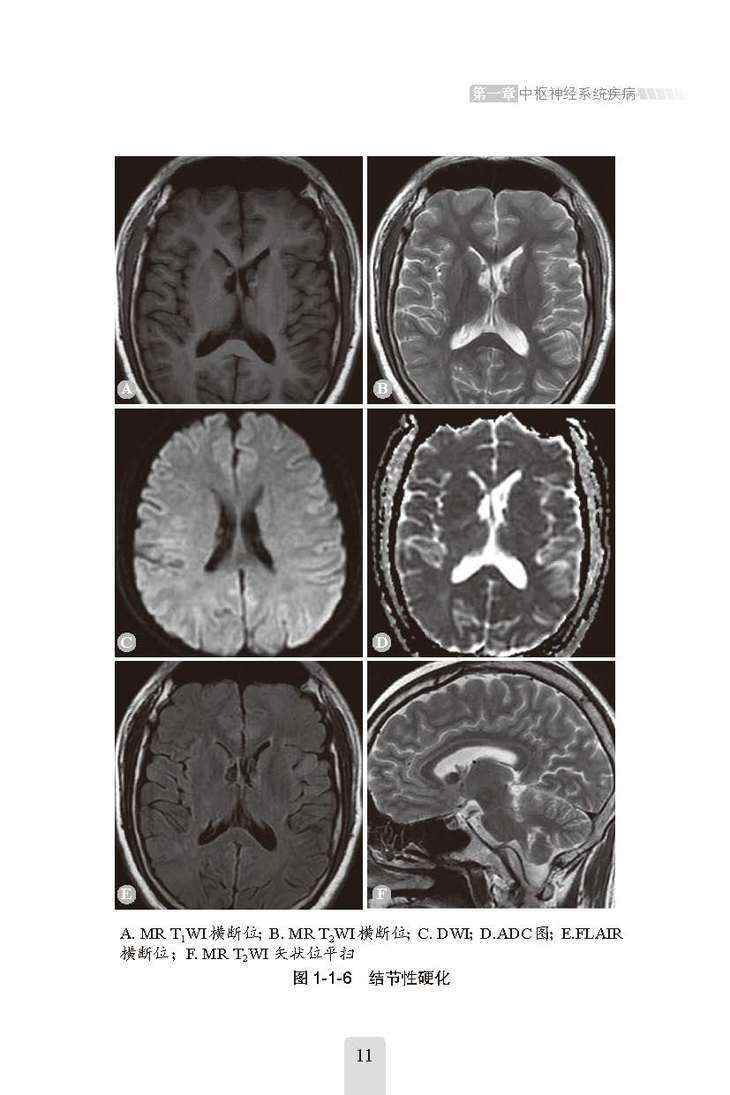

全书共9章、52节,主要讲述了中枢神经系统疾病、头颈五官系统疾病、呼吸系统疾病、循环系统常见疾病、消化系统常见疾病、泌尿系统与肾上腺疾病、腹膜后间隙及腹腔内病变、生殖系统与乳腺常见疾病、骨关节系统疾病,从每种疾病的“影像学检查方法选择”“临床概述”“影像学特点”和“鉴别诊断”等方面进行论述,详细讲解了每种疾病的各个影像学特点,并对易混淆疾病做了全面的鉴别诊断分析,避免了漏诊、误诊的可能。